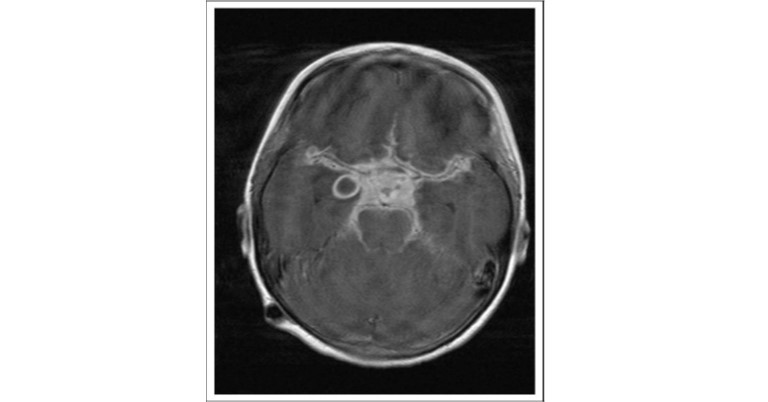

- CSF studies reveal lymphocytic pleocytosis, elevated protein and mildly reduced glucose. Neuroimaging (MRI preferable to CT) may reveal the lesions affecting the brainstem, basal ganglia, and midbrain (Fig 1).

Fig 1: T1-weighted post gadolinium magnetic resonance imaging (MRI) scan demonstrates enhancement of the whole suprasellar cistern with displacement and compression of the optic nerve anteriorly. A ring-enhancing abscess associated with the right temporal lobe is also visible.